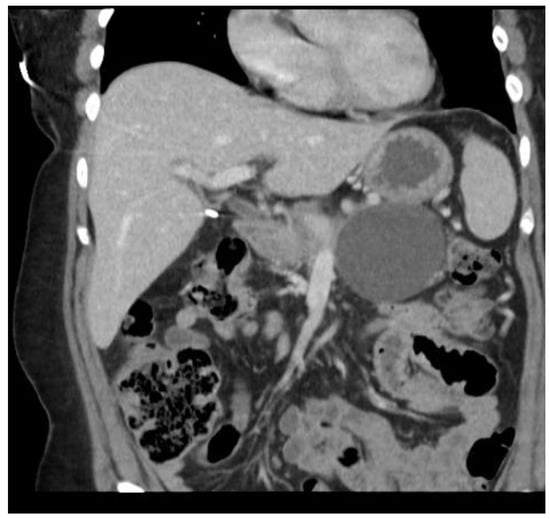

Multiple cytokines mediate a powerful pro-inflammatory immune response, such as tumor necrosis factor-alpha (TNF-a) and interleukins 1a, 1b, 6, and 18, exacerbating the initial pancreatic injury [37]. Pathologically, this appears as inflammation and can also be associated with a hemorrhage at the microscopic level (Figure 2 and Figure 3). The cytokine-mediated inflammatory cascade then extends the inflammatory cascade via lymphatic and systemic circulation into the liver, lungs, heart, kidneys, and gastrointestinal (GI) tract, leading to multi-organ injury [38]. This can cause systemic inflammatory response syndrome (SIRS), an early clinical feature that persists in cases of severe acute pancreatitis. Inflammation and damage to the GI tract can lead to bacterial translocation [39], and the species of bacteria involved are a predictive factor of disease severity, with Enterococcidae most frequently being associated with severe disease [40]. Obesity is also a predictive factor for moderate severity, and it leads to further deleterious effects through adipocyte lipolysis in the pancreas and adipose tissue [41,42] (Figure 2 and Figure 3).

3.2. Severity of Pancreatitis

The prediction of severity is made upon the admission of the patient, but the actual degree of severity is determined once sufficient time has elapsed in order to make a better assessment of acute pancreatitis. The most widely accepted classification of severity is the Revised Atlanta Classification (RAC) [4], which classifies pancreatitis as follows: (1) mild acute pancreatitis with no local inflammation or organ failure, (2) moderately severe acute pancreatitis with transient organ failure (<48 h) or local complications, and (3) severe acute pancreatitis with persistent organ failure (>48 h). In total, 65–70% of patients with acute pancreatitis have an uncomplicated course in which the symptoms resolve within a few days [4,43]. A total of 20–25% of patients develop moderate acute pancreatitis with local pancreatic injury fluid collection or necrosis, leading to prolonged hospitalization. This progression is displayed in Figure 4, Figure 5 and Figure 6. About 10% of patients develop severe acute pancreatitis accompanied by severe pain, a nutritional deficit, and a hospital stay > 4 weeks. These patients require highly intensive critical care with interventions (as indicated) [24].

Figure 1. Severe necrotizing pancreatitis.